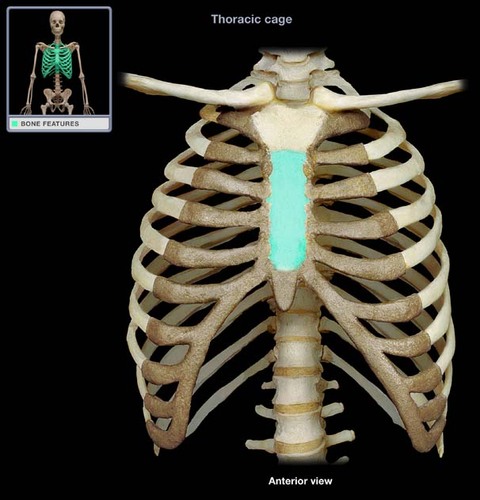

sterum

29

New cards

Sternum body

30

New cards

sternum manubrium

31

New cards

sternum xiphoid process